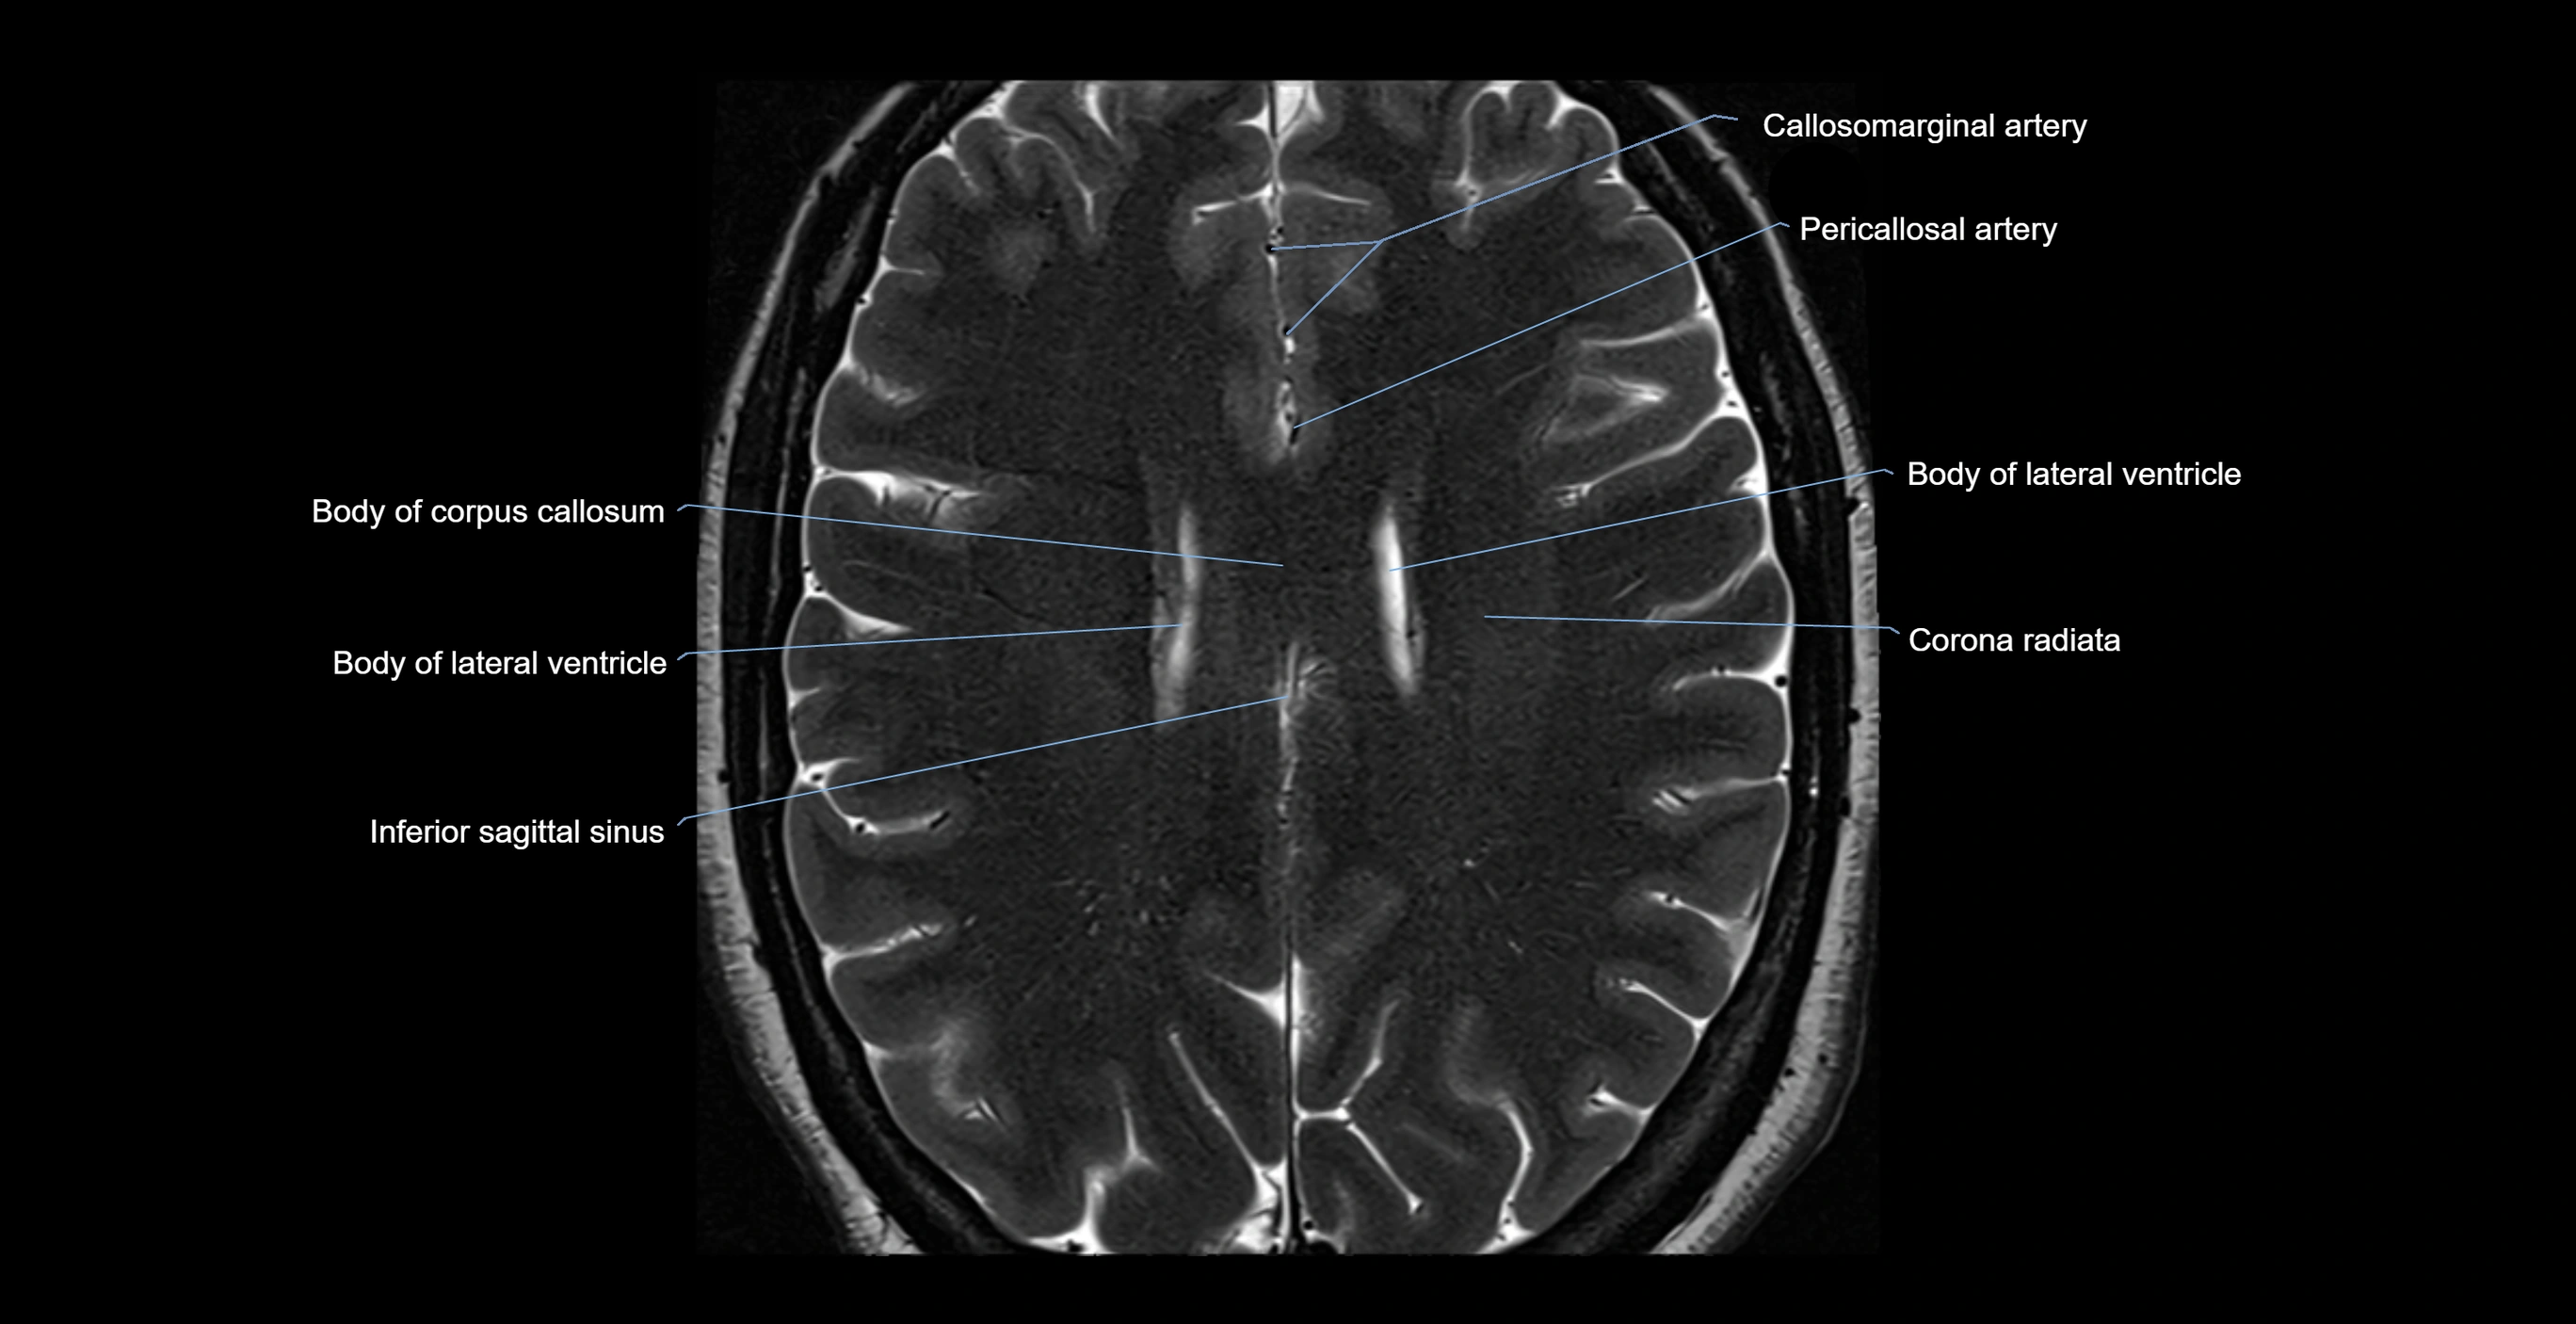

MRI images